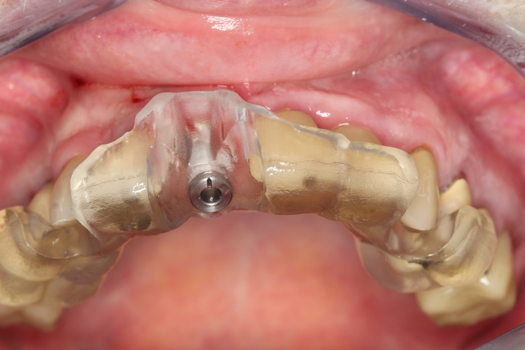

On the day of surgery, the plan was to extract teeth Nos. 21, 23, 24, 25, and 26, place 3.0 x 13-mm implants in the anterior region due to limited spacing, and place a 4.1 x 10-mm implant in the No. 21 extraction site. Before the extractions were performed, the No. 23 pontic was sectioned from the existing 2-unit cantilevered bridge utilizing ceramic and metal high speed rotary cutting burs ZR 6881 and H34L (Komet-USA), respectively. After removal of the pontic and extractions, the surgical guide was verified to be seating positively (Figure 36 through Figure 38). Surgical guide protocol was followed, and all implants were successfully placed and torqued to a value of greater than 35 Ncm (Figure 39 and Figure 40). All implants were placed without flapping, with the exception of No. 23. The flap was elevated to reposition lingual keratinized tissue facially for enhanced esthetic tissue profile. The implants were then prepared with a high-speed carbide bur (Komet-USA) with copious amounts of water (Figure 41 and Figure 42). The one-piece 3.0-mm diameter implant served the needs of the patient's spacing requirements. Inter-occlusal space requirements and path of draw were verified. The PMMA provisionals were air abraded and relined with crown-and-bridge material (Figure 43 through Figure 45).

Fig 41. Abutment preparation.

Figure 41

Fig 42. Occlusal view of prepared implants.

Figure 42